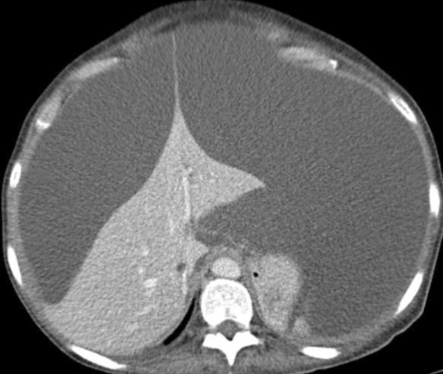

肝转移瘤可引起肝包膜凹陷,尤其见于原发肿瘤含有纤维成分时,如乳腺癌、肺癌、结肠癌及类癌等。但是转移瘤引起的肝包膜皱缩更常见于化疗或放疗后,乳腺癌等化疗后可引起假性肝硬化,可能与肿瘤浸润所致肝脏结构异常及药物化疗的毒性作用有关,具体可见往期连接→肝硬化没你想得那么简单,几种可能误诊为肝硬化的情况。

黑色素瘤肝转移,肝形态不规则、密度欠均匀,多处包膜凹陷,另见腹水及腹膜转移灶。

乳腺癌肝转移,化疗前可见肝内多发转移灶,化疗结束后可见肝体积缩小,肝包膜凹陷,类似于肝硬化。